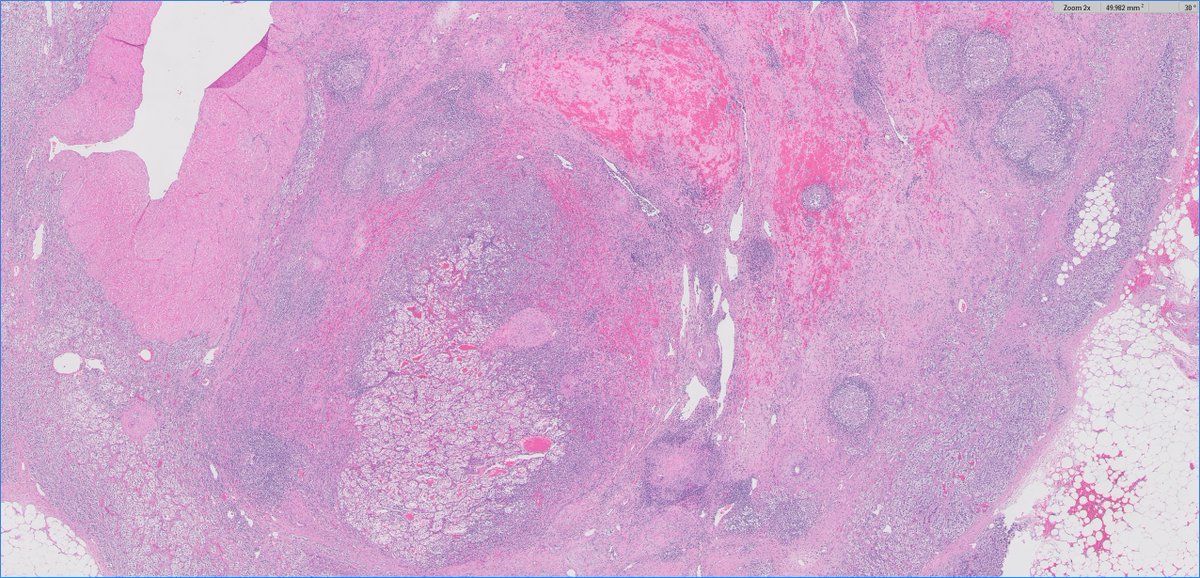

Uniquely intricate morphological pattern in #renal tumor! Catchy for #OnePicDx! 🔍 What is your diagnosis on this #nephrectomy #GUPath tweeps? Answer in comment👇👇👇